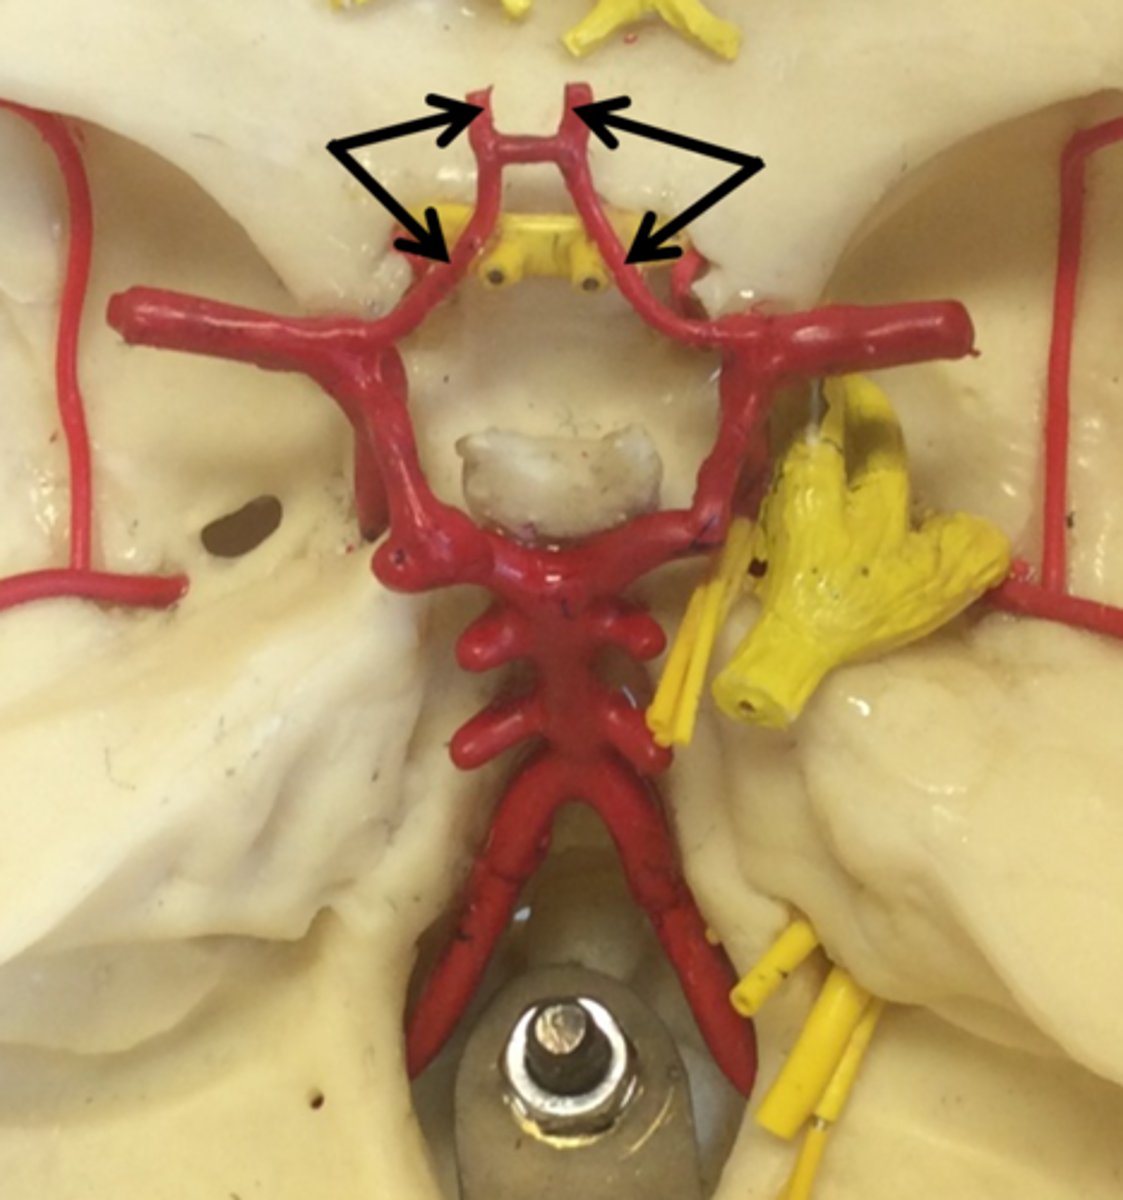

anterior communicating artery

Connects the two anterior cerebral arteries before they enter the median longitudinal fissure

posterior communicating artery

small arteries that connect the posterior cerebral and internal carotid arteries.

basilar artery

arises from the vertebral arteries and runs along the pons before dividing into posterior cerebral arteries.

vertebral arteries

Arteries that ascend the vertebrae, enter the base of the skull, and join together to form the basilar artery. Travel through foramen magnum to reach the pons.

internal carotid arteries

this artery branches off the common carotid arteries, travel up into the skull through the carotid canal, and then divide to form the anterior and middle cerebral arteries.

anterior cerebral arteries

two large arteries, arising from the internal carotid arteries. Travels anteromedially to the median longitudinal fissure where it supplies the superior and medial aspects of the frontal and parietal lobes.

posterior cerebral arteries

Two large arteries, arising from the basilar artery, that supply the posterior aspect of the brain, including the occipital lobes, as well as the inferior portion of the temporal lobes.